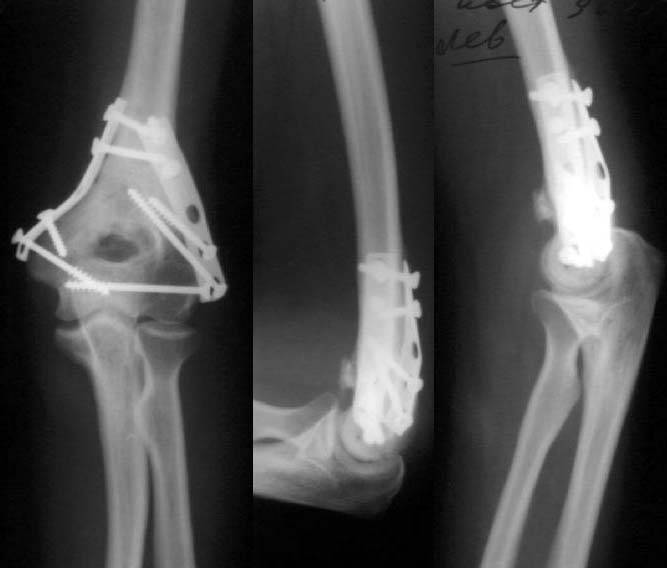

Результат в 6 месяцев

Лечение тут, видимо, должно основываться в первую очередь на открытой репозиции, поскольку возможности закрытой при таких повреждениях далеко недостаточны. Если поверхность блока состоит не просто из двух крупных фрагментов, лучше идти с отсечением локтевого отростка. Вопрос о методе фиксации более второстепенный. Можно и аппаратом. В приложении - пример лечения такого повреждения с внутренней фиксацией.